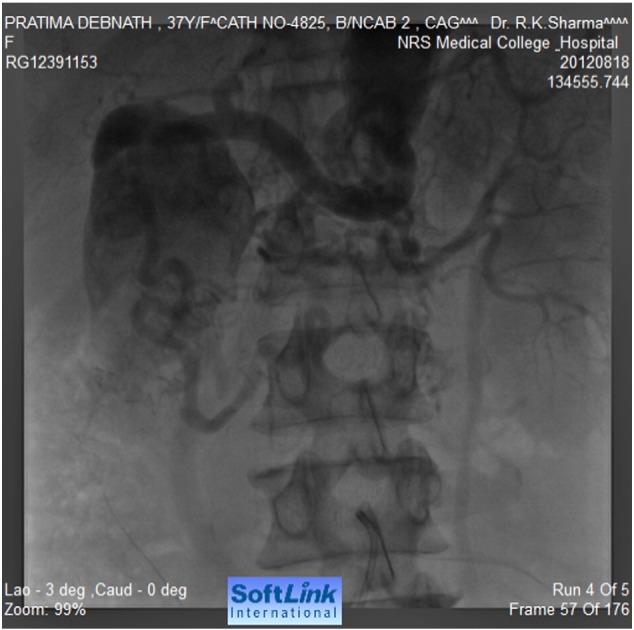

•Here, we are presenting a very rare case of coarctation of abdominal aorta where a transcatheter closure by a vascular plug of the feeding collateral to a large aneurysm has been done. To the best of our knowledge, this mode of therapy has never been described in persons with coarctation of abdominal aorta.•Aneurysms in patients with an abdominal coarctation are not well recognized. This is probably the only case being reported where transcatheter closure of the feeding vessel to the aneurysm has been successfully performed.•In this case, aneurysm was closed by a vascular plug only to prevent sudden rupture and death, and no attempt was made for stenting or dilatation of the atretic segment as the segment was long and no direct connection could be noted between upper and lower segments. The incidence of coarctation of the abdominal aorta is rare and the possibility of aneurysms in coarctation of the abdominal aorta is very rare compared to coarctation of the descending thoracic aorta. Thus, this case is being reported in view of the extreme rarity of the problem.